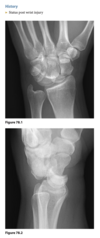

A 21-year-old man with worsening pain in the left wrist after an injury 6 months earlier (Fig. 2.13.1).

Figures 2.13.2 and 2.13.3 are of a 46-year-old man with wrist pain

Anteroposterior view of the left wrist

(Fig. 2.13.1) shows an ulna that is shorter than the

radius (i.e., negative ulnar variance or ulnar minus

variance) and a lunate that is sclerotic and some-

what irregular in shape.

Kienböck disease (i.e., lunatomalacia)

Kienböck disease, or lunatomalacia, is

osteonecrosis of the lunate. It is most common in

­ patients 20 to 40 years old and has a predilection

for the dominant hand in individuals involved

in manual labor.

Cause unknown

shortened ulna

in relation to the radius (i.e., negative ulnar variance

or ulnar minus variance) is seen in up to 75% of pa-

tients with lunatomalacia and is considered a major

cause of the disorder

The imaging findings, which do not always corre-

late with the patient’s symptoms, include increased

density or sclerosis of the lunate and, eventually, alteration in the normal bony shape with collapse

on radiographs.

For example, in a 46-year-old

man with wrist pain, a coronal T1-weighted image

(Fig. 2.13.2) demonstrates low signal intensity in

the lunate (arrow) and negative ulnar variance. The

gradient-recalled echo MR image (Fig. 2.13.3) shows

the signal intensity within the lunate to remain low

(arrow). These features are diagnostic of osteone-

crosis (i.e., Kienböck disease). Surgical intervention

includes lunate replacement, radial shortening, and

ulnar lengthening.